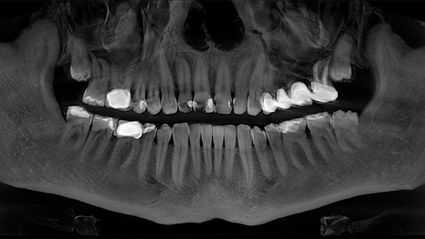

Da ich von dem Konzept zu 100% überzeugt bin, habe ich mich im Februar 2018 für eine Operation bei Dr. Ulrich Volz in der Swiss Biohealth Clinic entschieden. Unter örtlicher Betäubung entfernte Dr. Volz vier Bleichzähne und einen wurzelbehandelten Zahn (27). Er implantierte drei SDS-Keramikimplantate in den linken Oberkiefer, inklusive Sinuslift.